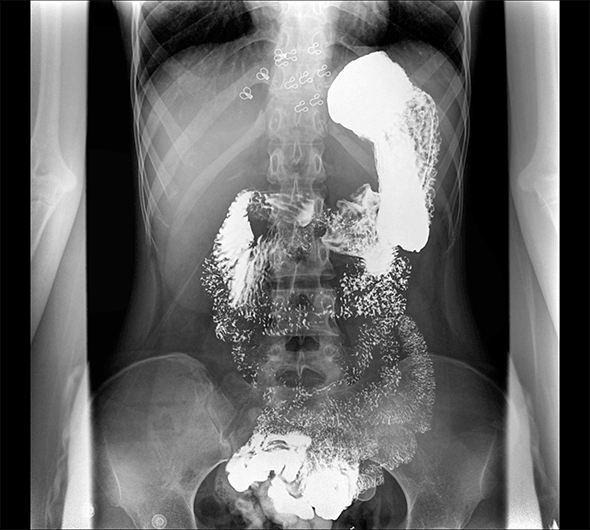

临床图像